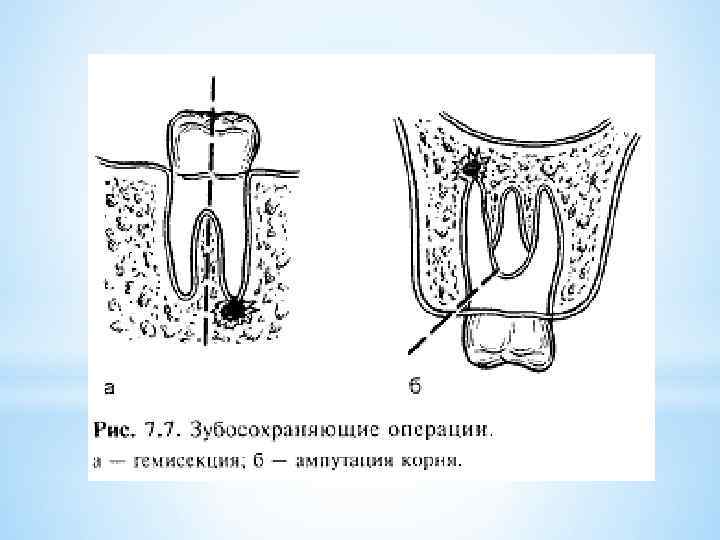

*Гемисекция зуба — это операция по удалению одного из корней многокорневого зуба вместе с прилегающей коронковой частью. Гемисекция зуба проводится в случае, когда очаг хронической инфекции уже не поддается консервативному лечению, локализуясь в одном из корней многокорневого зуба, а другие корни и часть коронковой части сохранны и готовы для того, чтобы на них проводить протезирование зубов.

*Гемисекция зуба — это операция по удалению одного из корней многокорневого зуба вместе с прилегающей коронковой частью. Гемисекция зуба проводится в случае, когда очаг хронической инфекции уже не поддается консервативному лечению, локализуясь в одном из корней многокорневого зуба, а другие корни и часть коронковой части сохранны и готовы для того, чтобы на них проводить протезирование зубов.

При гемисекции зуба под местной анестезией проводится вертикальное рассечение многокорневого зуба с последующим удалением той части, в области верхушки корня которой имеется хронический очаг инфекции. Перед операцией гемисекции хирург пломбирует каналы корней зубов, подлежащие сохранению. Иногда при гемисекции врачу приходится отслаивать слизистонадкостничный лоскут, после чего с помощью бормашины удаляется поврежденный корень. Зуб после гемисекции полностью сохраняет свою функциональность и может быть использован для установления ортопедических конструкций.

При гемисекции зуба под местной анестезией проводится вертикальное рассечение многокорневого зуба с последующим удалением той части, в области верхушки корня которой имеется хронический очаг инфекции. Перед операцией гемисекции хирург пломбирует каналы корней зубов, подлежащие сохранению. Иногда при гемисекции врачу приходится отслаивать слизистонадкостничный лоскут, после чего с помощью бормашины удаляется поврежденный корень. Зуб после гемисекции полностью сохраняет свою функциональность и может быть использован для установления ортопедических конструкций.

*Возможно два варианта проведения операции гемисекции. *В первом случае принцип хода операции следующий. Производится сепарация коронки, то есть коронку распиливают до области бифуркации (места разделения на корни), после чего происходит удаление корня. *Другой вариант – лоскутный метод. Хирург отслаивает слизисто-надкостничный лоскут, после чего вырезает причинный корень. Освободившуюся полость заполняют веществом, способствующим заживлению тканей. Лоскут возвращается на место и ушивается. *

*Возможно два варианта проведения операции гемисекции. *В первом случае принцип хода операции следующий. Производится сепарация коронки, то есть коронку распиливают до области бифуркации (места разделения на корни), после чего происходит удаление корня. *Другой вариант – лоскутный метод. Хирург отслаивает слизисто-надкостничный лоскут, после чего вырезает причинный корень. Освободившуюся полость заполняют веществом, способствующим заживлению тканей. Лоскут возвращается на место и ушивается. *